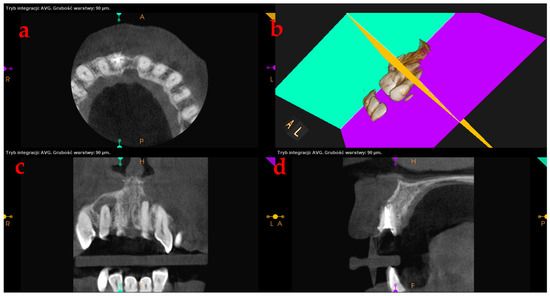

Prior to treatment as well as during the whole procedure, the analysis of computed tomography scans was performed. The opposite of a 2D X-ray, this is a procedure that requires time to carefully evaluate each plane. To obtain a precise radiological image, a pantographic curve should be drawn, as shown in Figure 1. The analysis of each of the resulting planes: transverse, longitudinal, and axial, can be carried out with an accuracy of 0.1 mm. Table 1 lists the items that are assessed pre-treatment on CBCT scans.

To diagnose the case and choose an effective treatment method, it is necessary to carefully analyze each of the planes, which are presented in Figure 2. In the upper right window, the CT scanner application software generates a three-dimensional image of the bone structure with teeth. However, root canals are not visible here. In the next step, based on CT, a three-dimensional computer model of the bone structure (i.e., tooth and alveolar bone) is prepared. In the remaining three windows, pictures of the examined tooth’s cross-sections (namely, axial, transverse, and longitudinal) are visible.

Figure 1. The CT scan of a tooth with a pantographic curve, with the blue line marking the angle and perspective for the front view, can be generated separately. The red line marks the pantographic curve.

Figure 2. The procedure leading to the creation of a three-dimensional bone model is (a) a CT scan, axial tooth’s cross-sections, (b) a three-dimensional image of the bone structure and teeth; yellow: axial plane, green: longitudinal plane, pink: transverse plane, (c) tooth’s transverse cross-sections, and (d) tooth’s longitudinal cross-sections.